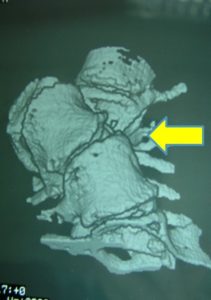

Εικόνα 8 : Τρισδιάστατη (3-D) αξονική τομογραφία της Θωρακοοσφυϊκής Μοίρας της Σ.Σ. Μετωπιαία προβολή. Παρατηρείται η ύπαρξη ημισπονδύλου συνεπεία του οποίου προκλήθηκε η σημαντικοτάτη σκολιωτική παραμόρφωση της Σ.Σ. με το κυρτό προς τα δεξιά (βέλος). Διαπιστώνεται επίσης σημαντική ασσυμετρία των πλευρών. Οι πλευρές στο δεξιό μέρος του κυρτώματος είναι ιδιαίτερα λοξές σε σχέση με την Σ.Σ. ενώ οι φέρονται σχεδόν οριζόντια.